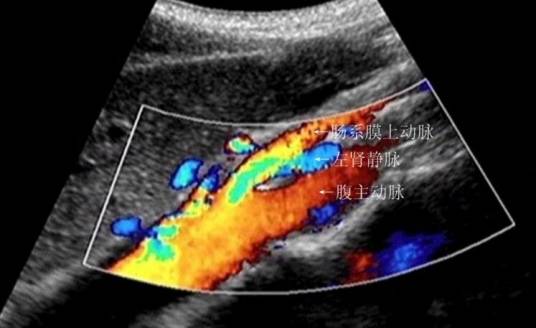

胡桃夹现象(nutcracker phenomenon)亦称左肾静脉压迫综合征,好发于青春期至40岁左右的男性,儿童发病分布在4-7岁,多发年龄见于13-16岁,是儿童非肾性血尿常见的原因之一,为左肾静脉汇入下腔静脉的行程中,因走行于腹主动脉和肠系膜上动脉之间形成的夹角受到挤压而引起的临床症状。临床上往往借助于超声来诊断,其诊断标准为:仰卧位左肾静脉狭窄前扩张部位近端内径比狭窄部位内径宽2倍以上,脊柱后伸位15-20分钟后,其扩张部位内径比狭窄部位内径宽4倍以上,取两个体位即可诊断。亦可采用综合指标,即有以上表现以外,再加上脊柱后伸位15~20分钟后,左肾静脉扩张近端血流速度≤0.09m/s,肠系膜上动脉与腹主动脉夹角在9度以内为参考值。